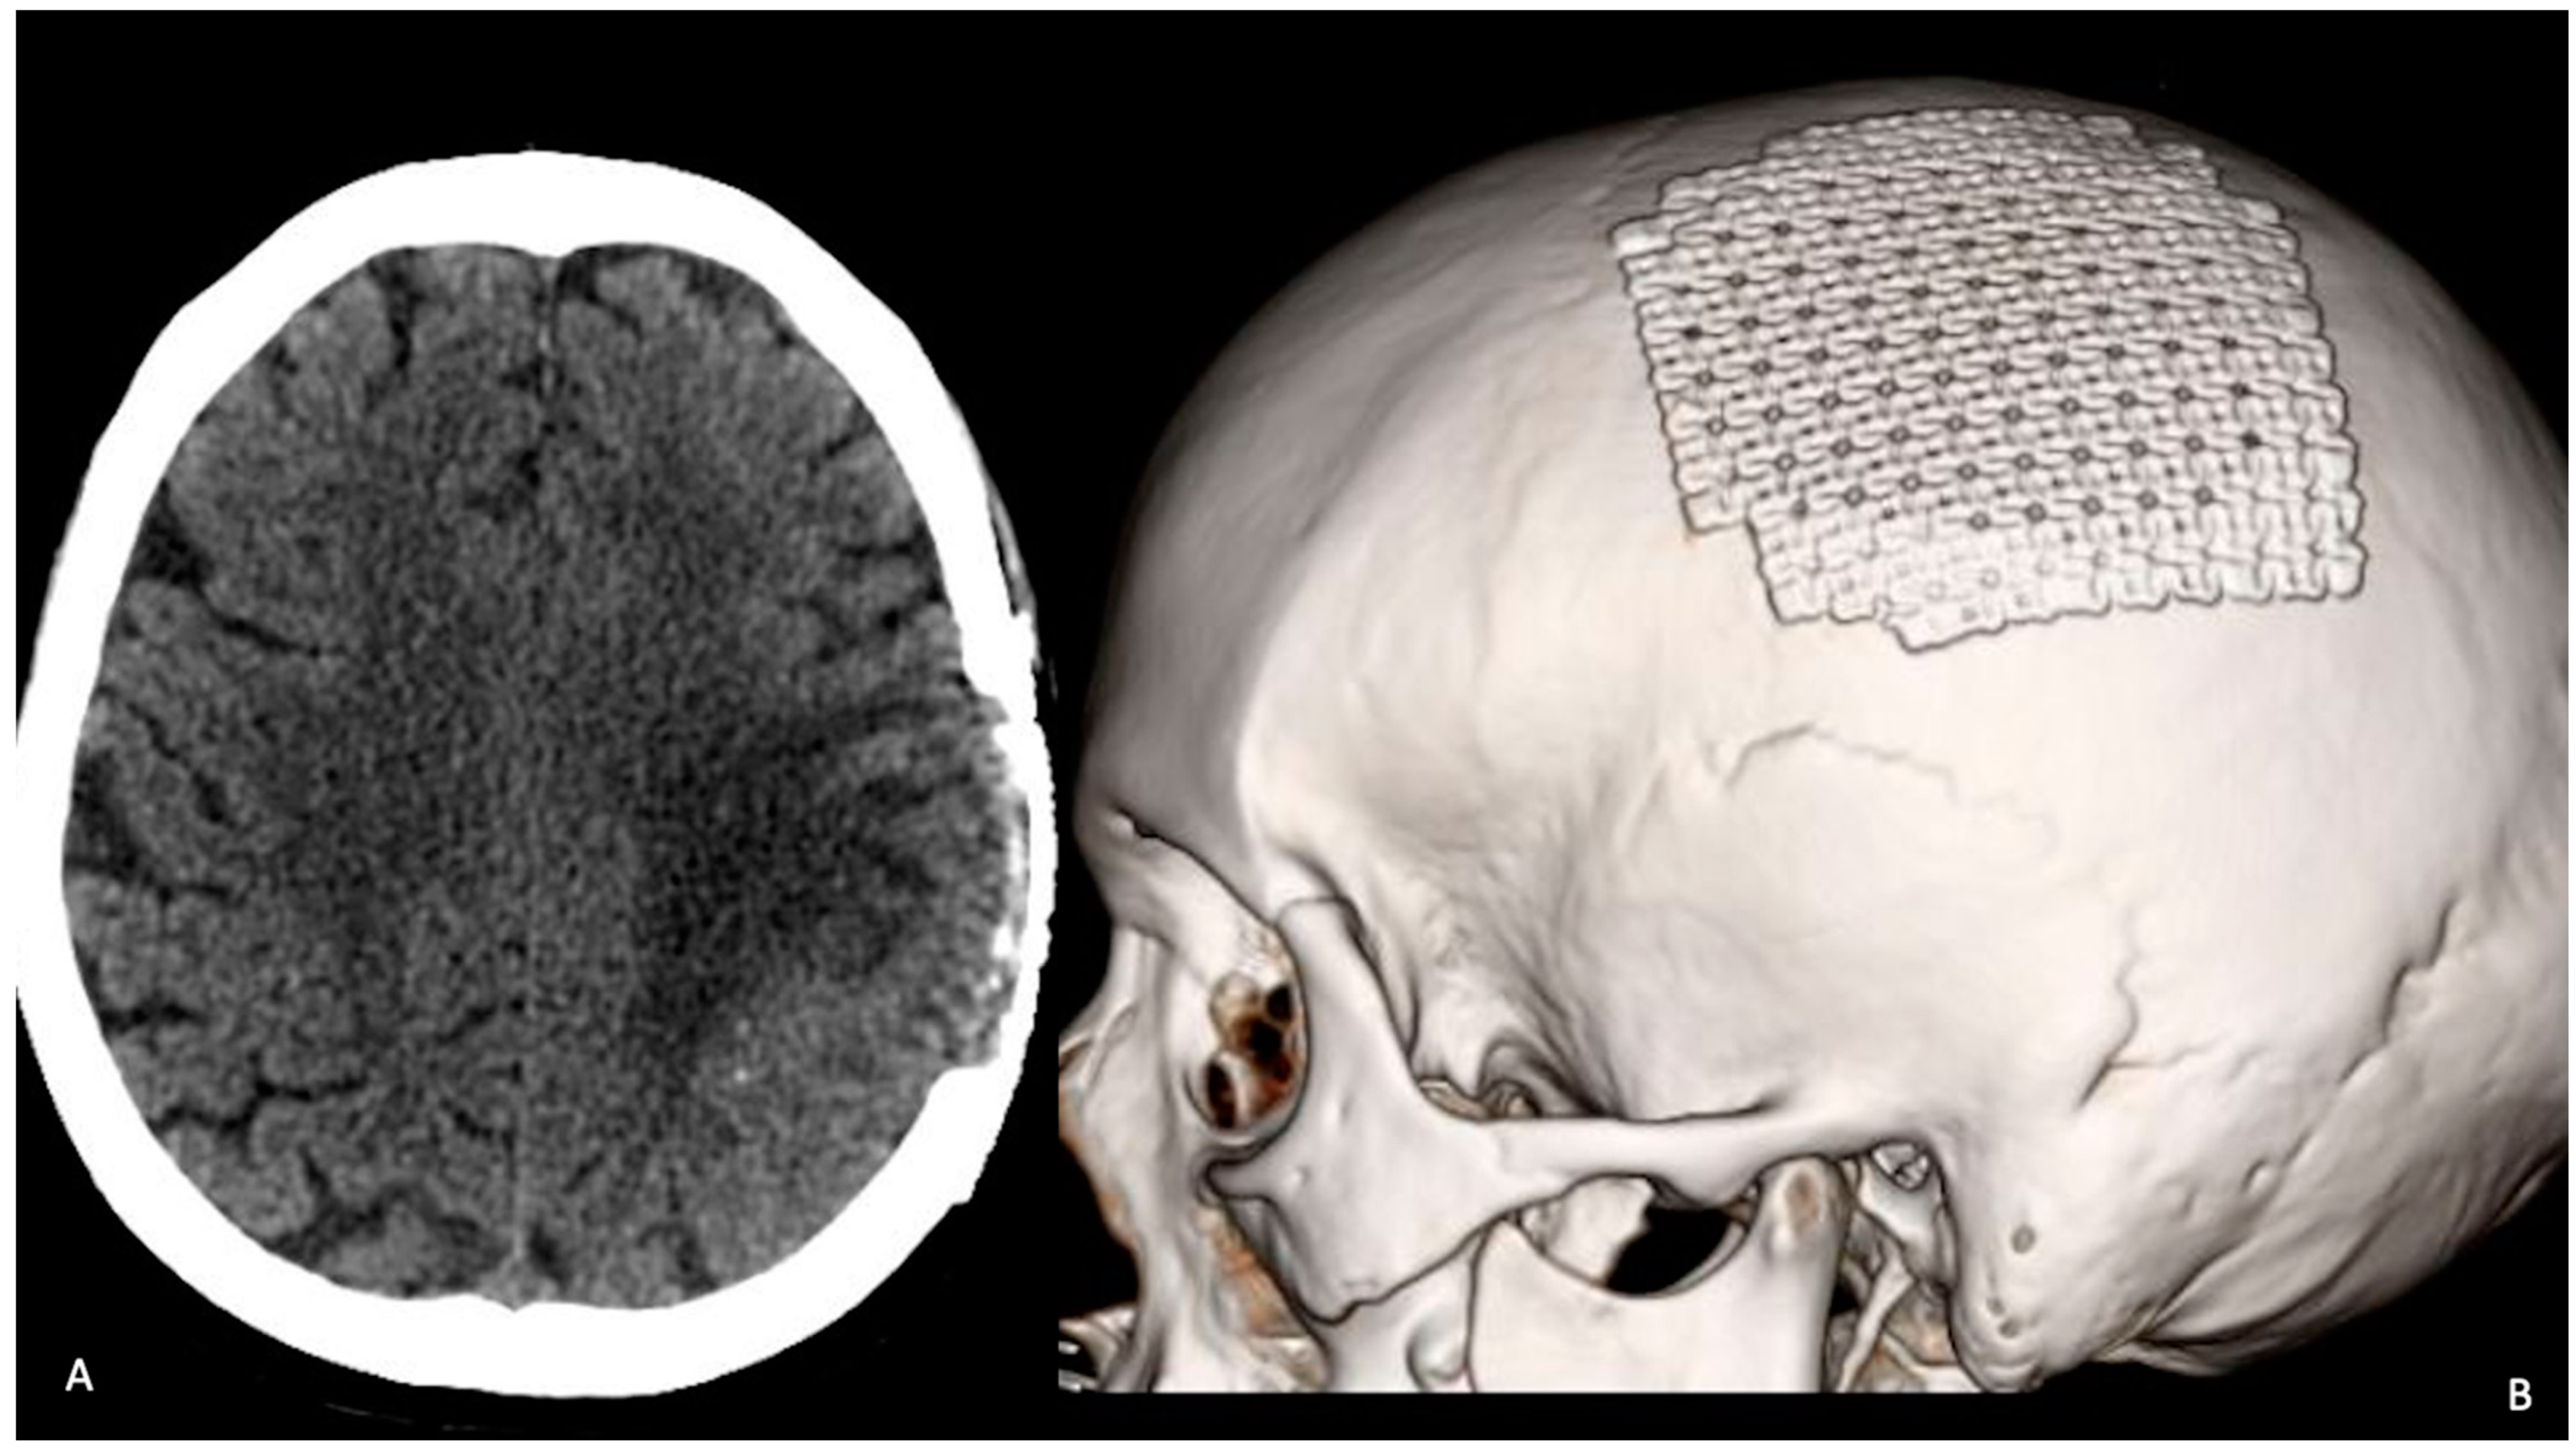

2. Case Description